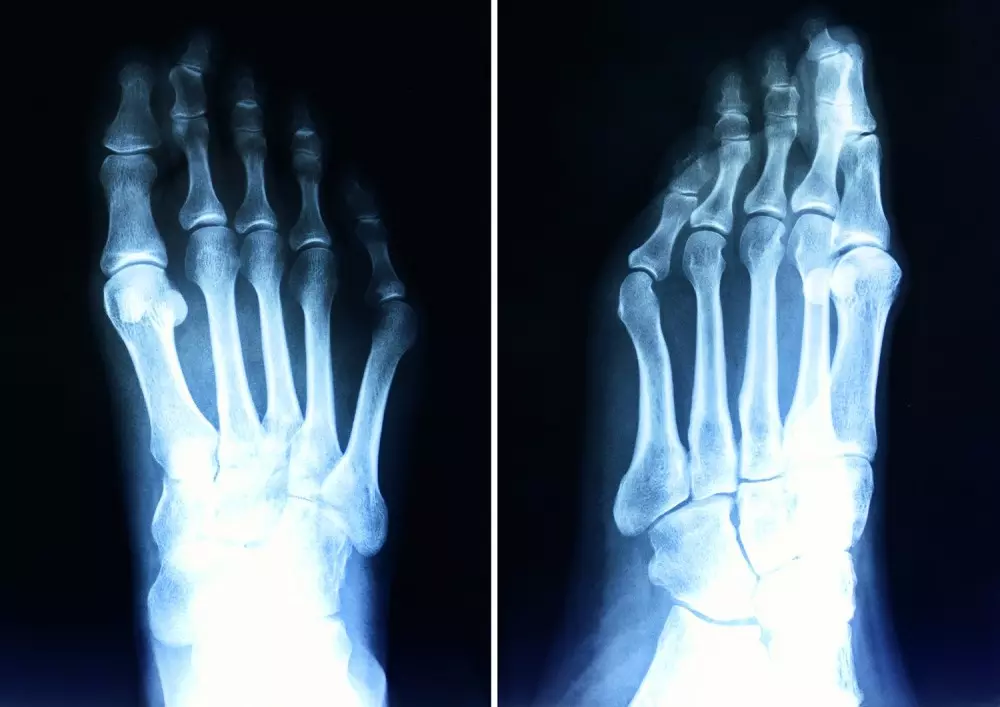

- hallux valgus – postępowanie fizjoterapeutyczne

W dziale „Z praktyki gabinetu” będą mogli zapoznać się Państwo z artykułem pt. „Hallux valgus – postępowanie fizjoterapeutyczne”. Haluksy to bardzo częsta deformacja w obrębie stopy, szczególnie u kobiet, co może być spowodowane źle dobranym obuwiem czy butami na obcasach. W tekście prezentujemy metody fizjoterapeutyczne stosowane w przypadku problemu, jakim jest hallux valgus: mobilizacje, stretching, autostretching, kinesiotaping oraz przedstawiamy odpowiednie zaopatrzenie fizjoterapeutyczne i działania profilaktyczne.